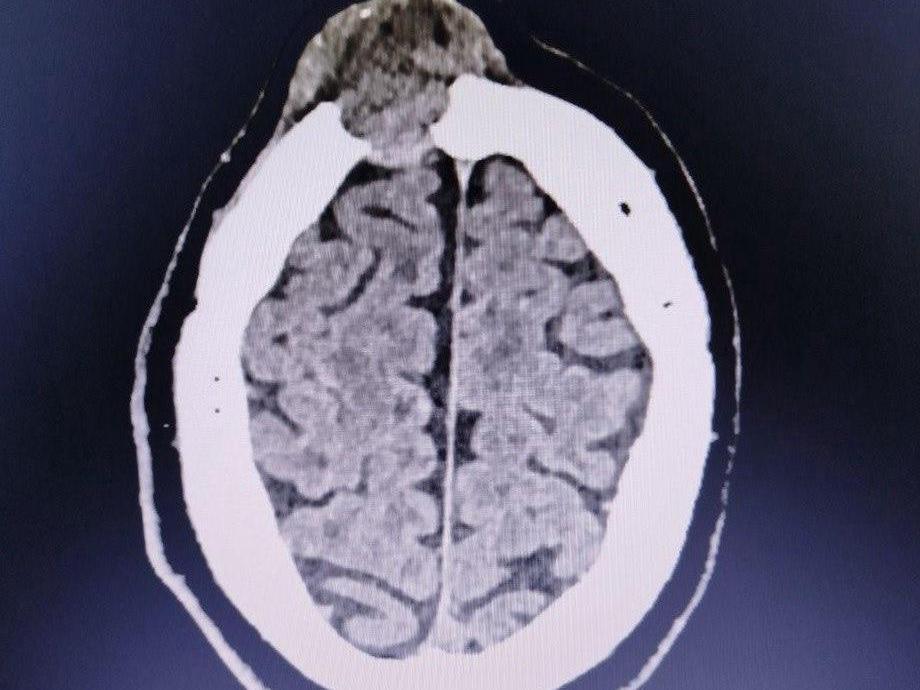

A CT scan revealed the forehead bump was actually a brain tumor eroding the patient«s skull.

Based on the results of a computed tomography scan, a tumor was diagnosed in the man. The neoplasm was already destroying the frontal bone of his skull.